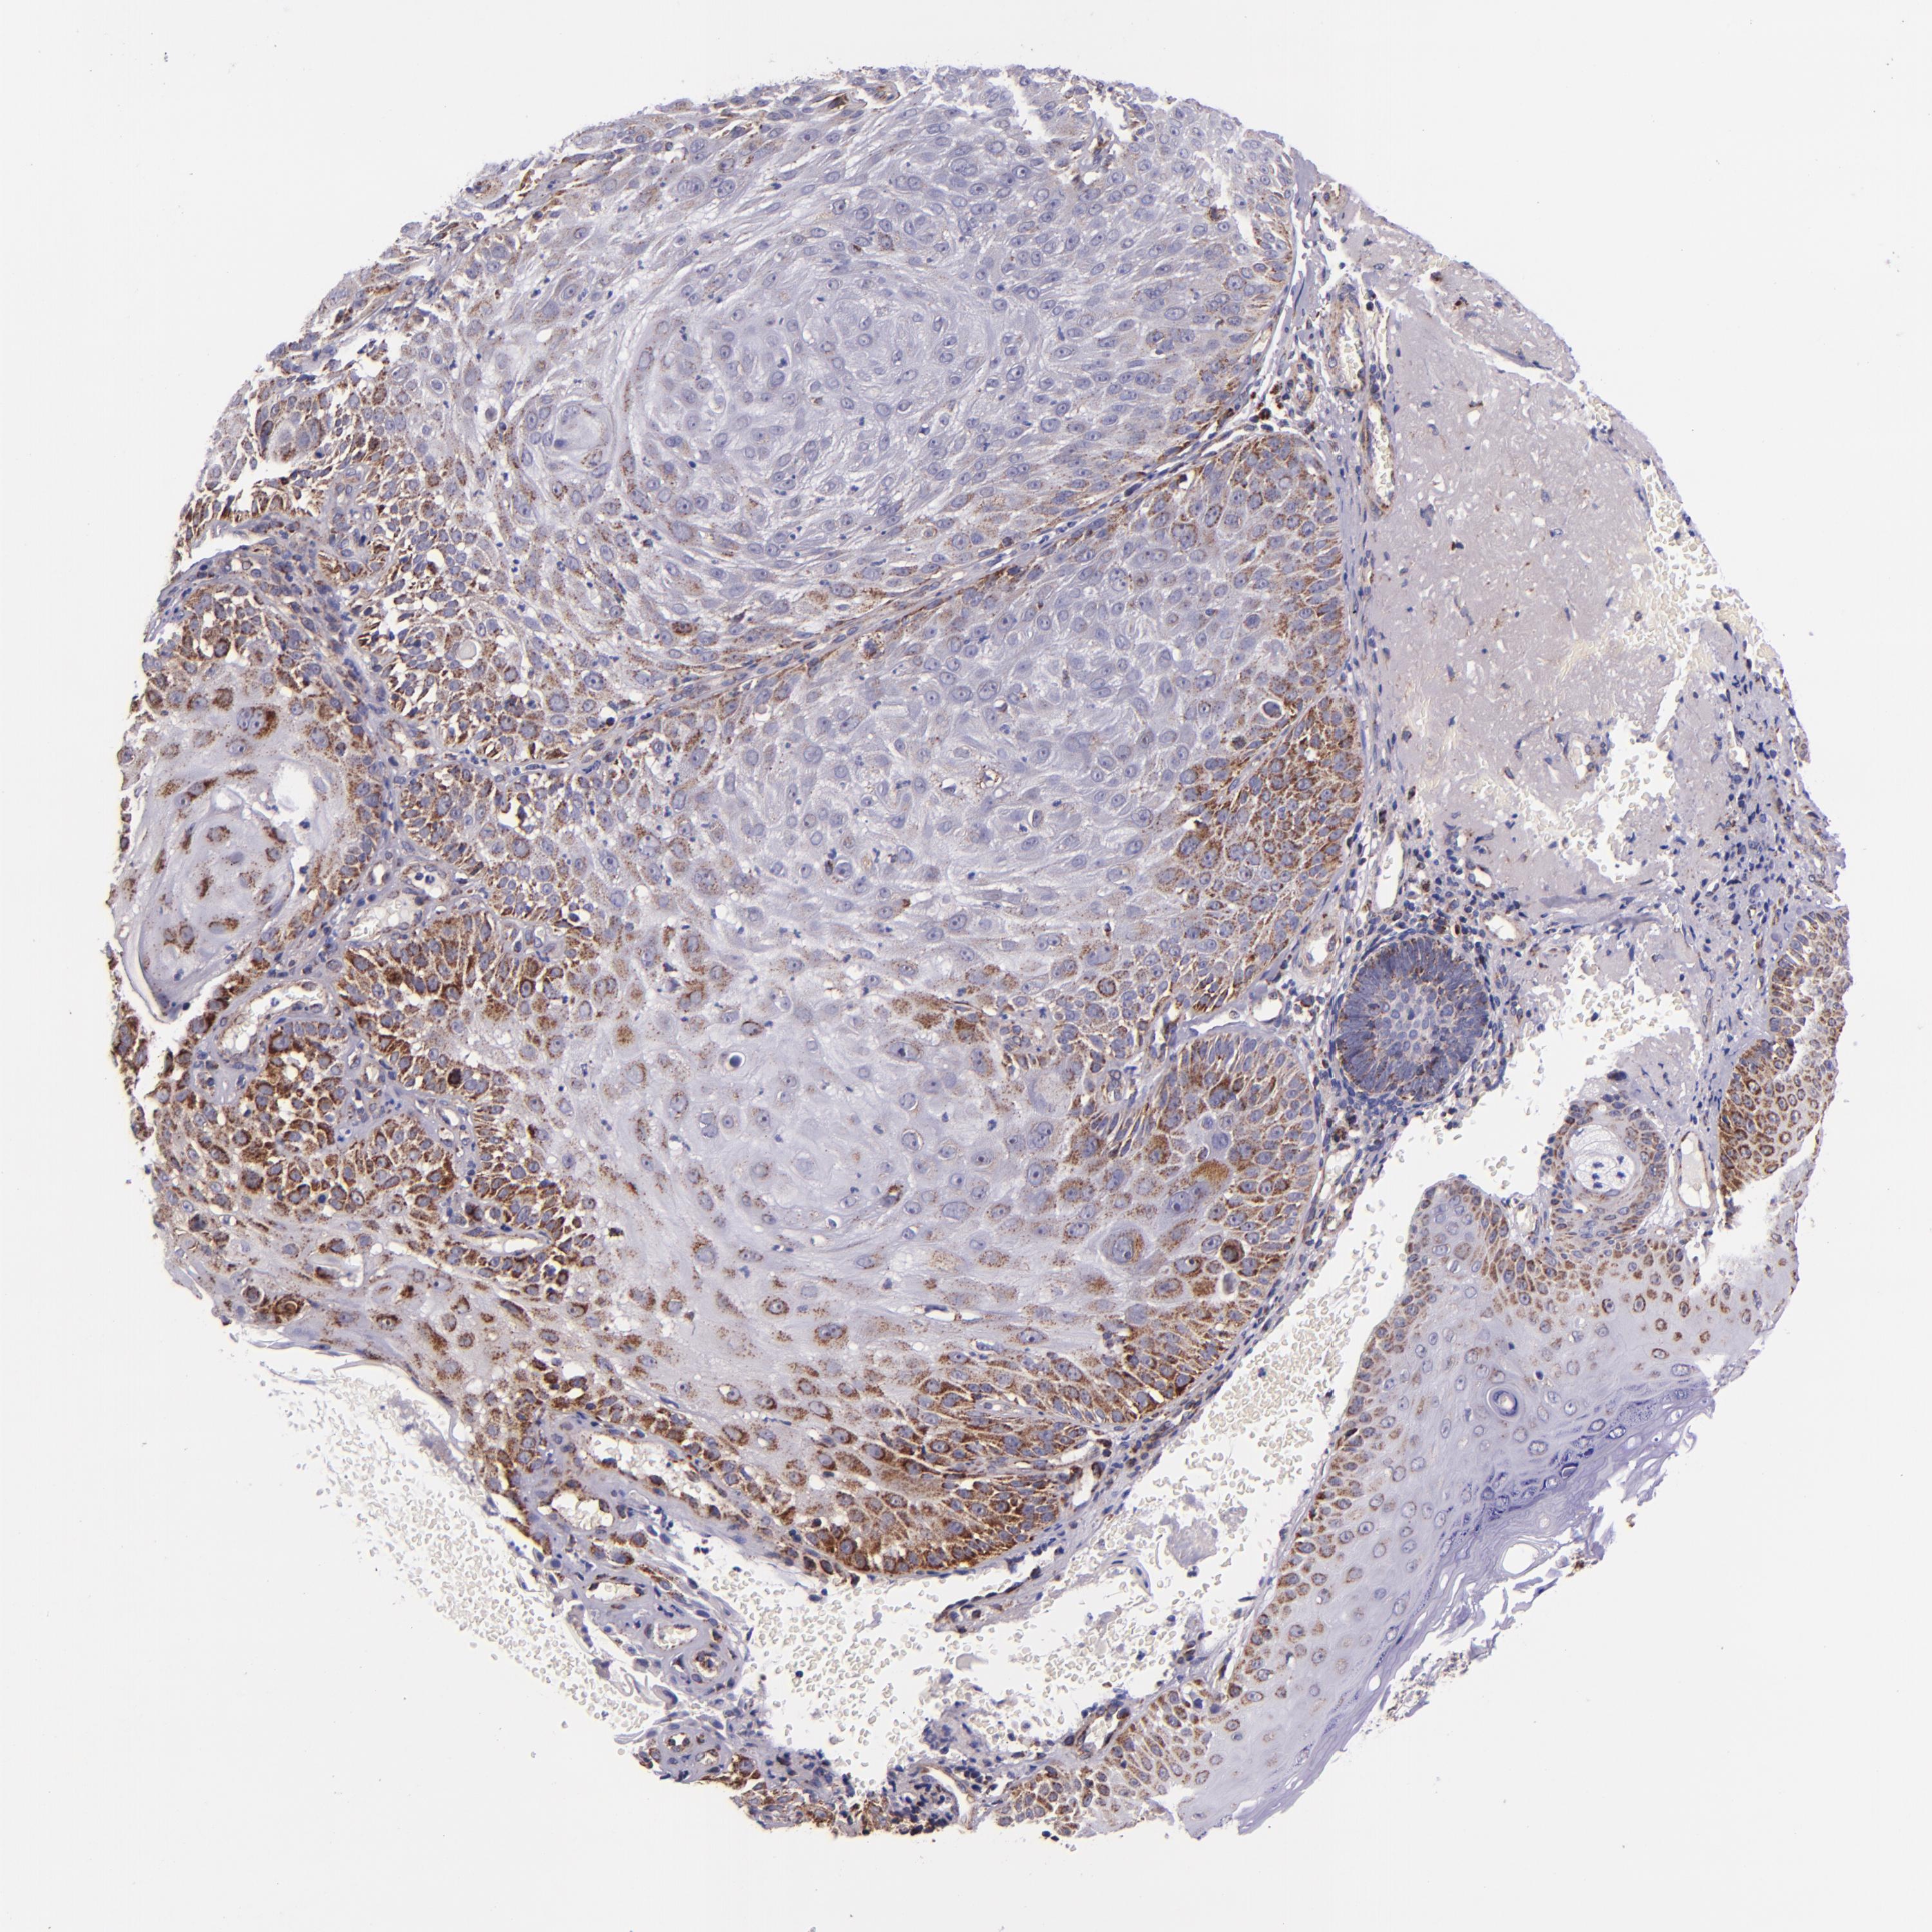

Basal cell and squamous cell cancer

SKIN CANCER - Protein expressioni

A mouse-over function shows sample information and annotation data. Click on an image to view it in a full screen mode. Samples can be filtered based on level of antibody staining by selecting one or several of the following categories: high, medium, low and not detected. The assay and annotation is described here.

Antibody stainingi

Antibody staining in the annotated cell types in the current human tissue is reported as not detected, low, medium, or high, based on conventional immunohistochemistry profiling in selected tissues. This score is based on the combination of the staining intensity and fraction of stained cells.

Each image is clickable and will lead to virtual microscopy that enables deeper exploration of all samples and also displays staining intensity scores, fraction scores and subcellular localization as well as patient and tissue information for each sample.

Antibody HPA000425

Antibody HPA002017

Staining

High

Medium

Low

Not detected

Intensity

Strong

Moderate

Weak

Negative

Quantity

>75%

75%-25%

<25%

None

Location

Nuclear

Cytoplasmic/membranous

Cytoplasmic/membranous,nuclear

Squamous cell carcinoma, NOS